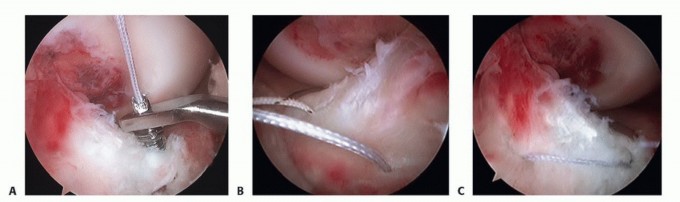

Attempt to reduce the fracture fragments as described earlier in the section “Fracture Reduction” (TECH FIG 1).

- TECH FIG 1 • A. Arthroscopic image taken of a type III tibial spine fracture. B. Arthroscopic image showing anatomic reduction of the fracture fragments.

TECH FIG 3 • Arthroscopic suture fixation. A,B. Two 1-0 PDS sutures are passed through the base of the ACL. A suture passer is used to grab the suture ends through a transphyseal tunnel and the suture ends are tied in the anteromedial border of the tibia. C. Final suture fixation of a tibial spine fracture.*

TECH FIG 4 • Arthroscopic suture anchor fixation. A. Two limbs of 1-0 PDS suture are passed through the base of the ACL at its insertion onto the tibial eminence and luggage tag the sutures. B. The limbs of suture are passed through suture anchors and secured anterior to the tibial eminence, angled slightly anterior to posterior. C. Final suture anchor fixation of a tibial spine fracture.